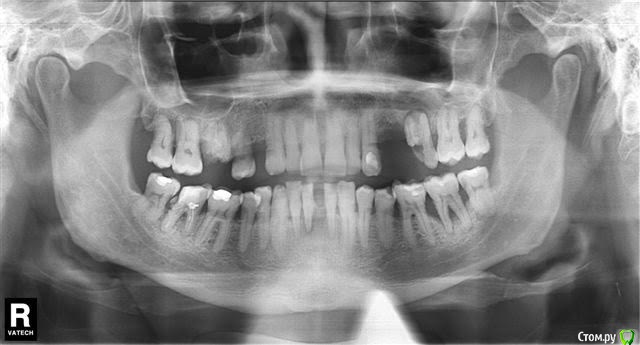

bobrdobr Опубликовано 12 ноября, 2016 Поделиться Опубликовано 12 ноября, 2016 Здравствуйте, уважаемые доктора! Однажды здесь мне уже помогли. Большое спасибо. Теперь тема касается родственника. Планируется удаление части зубов и протезирование на имплантах. Уже отсутствуют 14, 24, 25, 31 зубы, 16 и 26 разрушены, 41 шатается. Заранее извиняюсь за размер снимка. Полноразмерный снимок прикреплю через несколько дней. Вопросы:Под удаление 16, 26, 37 и 41, верно? Правильно понимаю, что в идеале нужно 2 импланта в область 14-16, 2 импланта в область 24-26, 1 имплант вместо 37 и 2 импланта в область нижних резцов? Можно ли где-то применить мост с опорой на существующие зубы? В каком порядке лучше протезироваться? Сделать все сразу не позволяет бюджет Заранее спасибо. Ссылка на комментарий

bobrdobr Опубликовано 14 ноября, 2016 Автор Поделиться Опубликовано 14 ноября, 2016 (изменено) Снимок в полном размере Изменено 14 ноября, 2016 пользователем bobrdobr Ссылка на комментарий